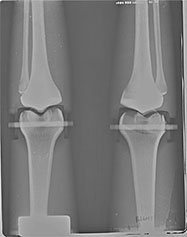

BREAK-APART PIXY Pelvis X-Ray BREAK-APART PIXY Knees X-Ray 1 BREAK-APART PIXY Knees X-Ray 2